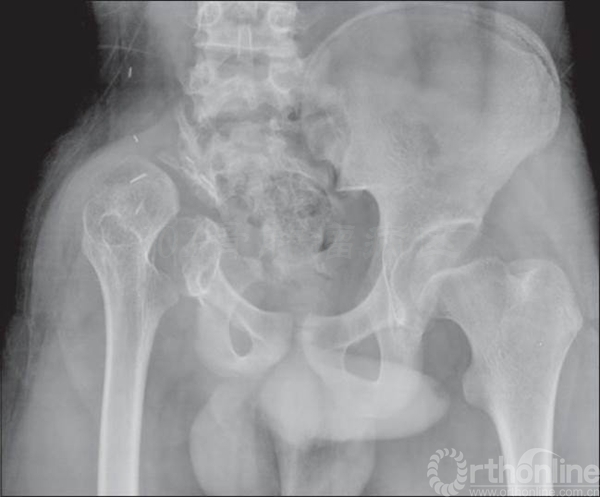

患者女性,术前X片提示:左侧骨盆Ⅱ+Ⅲ区溶骨性改变,诊断考虑骨巨细胞瘤合并动脉瘤样骨囊肿。血管栓塞后行骨盆Ⅱ+Ⅲ区切除,股骨头旷置术。术后病理报告是骨巨细胞瘤恶变,故行化疗6个月。术后13年随访,患者有跛行,但行走自如。

术前X线片